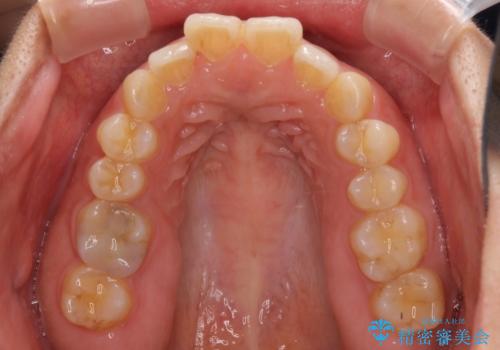

- 上下の前歯のでこぼこを気にして来院された患者様です。

結婚式が近いこともあり、全く目立たない裏側矯正により口元を整えることとしました。

下顎が左側にずれているため、裏側矯正ということもあり咬み合わせを整えるのに時間がかかってしまいました。